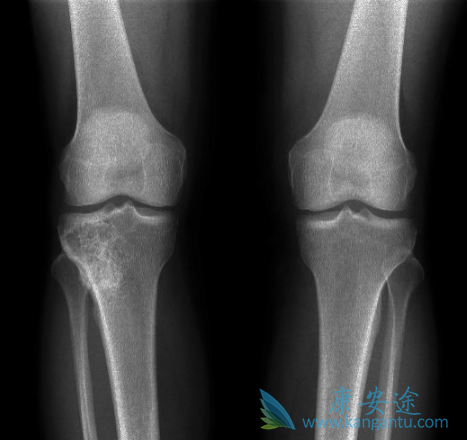

既往骨折史是未来脆性骨折强有力的预测因素之一。在FREEDOM研究中,地诺单抗(denosumab)可以显著降低患者新发椎体、非椎体以及髋骨骨折的风险。FREEDOM事后分析,旨在阐明地诺单抗在既往有骨折史的受试者二次脆性骨折预防中的疗效。共计8087名女性被随机分组接受每6个月皮下注射地诺单抗60 mg或者安慰剂治疗,共36个月。

为评估患者的二次脆性骨折,研究者通过患者的既往骨折情况以及年龄、既往骨折部位和骨质疏松症药物治疗史来分析地诺单抗的抗骨折疗效。据报告,总体研究人群中既往脆性骨折的发生率为45%。与安慰剂组相比,地诺单抗可显著降低(幅度为39%)患者的二次脆性骨折风险(发生率,17.3% vs. 10.5%);无论患者的年龄或既往骨折部位如何。

在总体人群中,与安慰剂组相比,地诺单抗(denosumab)可显著降低(幅度为40%)患者的脆性骨折风险(发生率,13.3% vs. 8.0%);无论既往骨质疏松症药物治疗史如何,研究人员都观察到了相似的结果。结论:在所有风险亚组中(包括那些既往有脆性骨折的患者),地诺单抗可使患者的脆性骨折风险降低到相似水平。